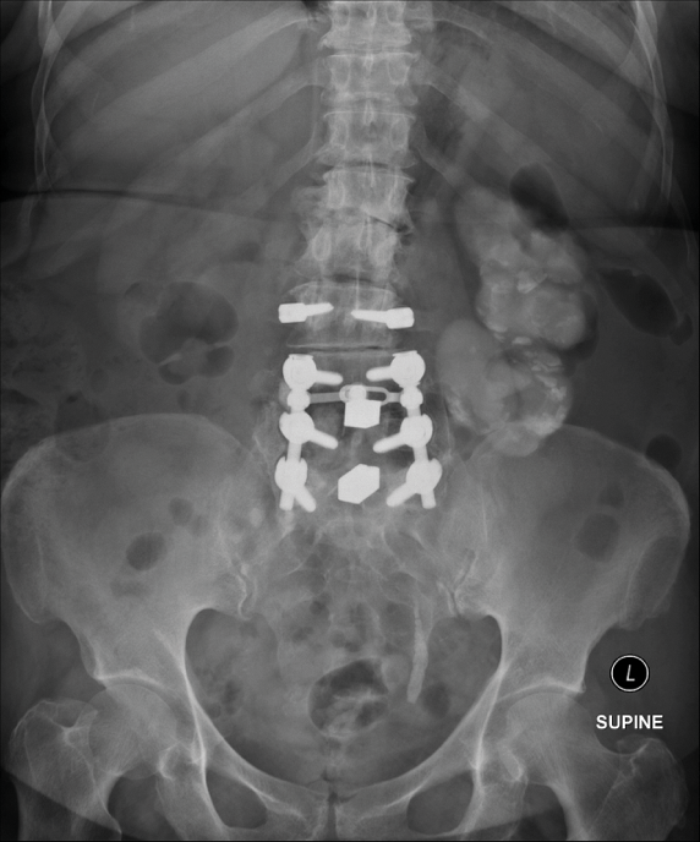

A 74 year old women presents with non-specific abdominal pain and has a plain X-ray KUB taken (Figure A). Subsequently the admitting team arrange a renogram (Figure B)

- What does the KUB x-ray and renogram show?

-

X-ray: amorphous dystrophic calcification (putty kidney) representing calcified caeseous tissue. Previous spinal stabilisation surgery and metalwork. Renogram: complete loss of function of the left kidney.

Renal tuberculosis commonly caused by mycobacterium tuberculosis bacilli; genitourinary TB accounts for 15-20% of extra-pulmonary TB.